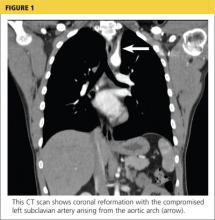

Because the diagnosis remained unclear, the patient was asked to bring the disc containing his chest CT images to the office. The radiologist, who was informed about the patient’s history and exam findings by phone, reviewed the CT images and felt there were changes surrounding the three branches off the aortic arch suggestive of inflammation, in addition to the stenosis at the left subclavian artery (see Figure 1 and Figure 2).